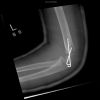

Displaced fracture of the lateral epicondyle of the humerus - post K-wire Fixation - Lateral view (4)